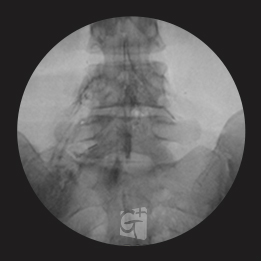

경추 신경성형술

경추 좌측 2번 신경절

경막외 카테터 삽입 -

척추관 안쪽으로 진입하여 약물 주입

원인부위 염증 제거 및 유착 박리

유착박리로 추간공 확보 신경 압박 감소

척추관에서 약물이 퍼져나오는 모습

목 신경 전체를 효과적으로 치료